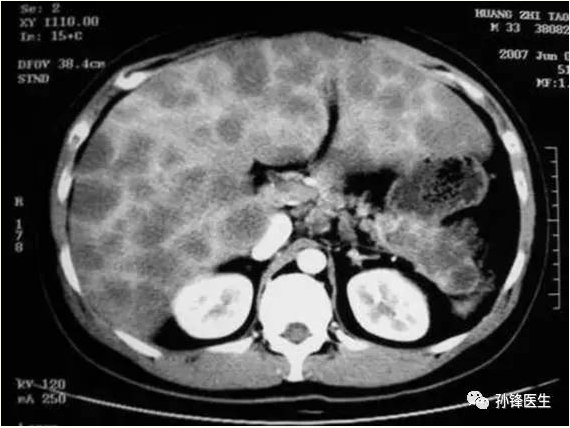

肝脏转移瘤ct1 mhc,胃癌(147580) 胃癌肝转移

术前ct提示肝右叶转移瘤

肝脏影像系列六肝内多发转移瘤